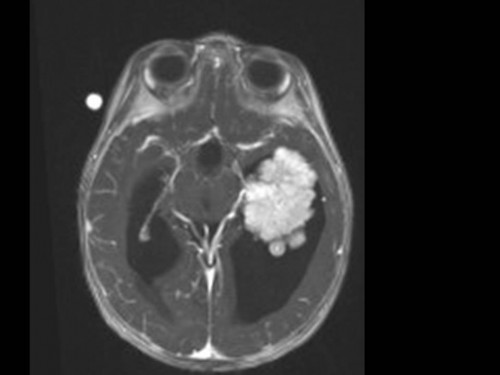

10 Monate altes Mädchen. Der Kinderarzt stellt fest, dass das kleine Mädchen einen recht großen Kopfumfang hat, nicht mit den Augen fixiert und anscheinend auch nicht richtig sehen kann. Damit bestätigt er die größten Befürchtungen der Eltern, denen in den letzten Wochen aufgefallen war, dass ihre Tochter nach keinem Spielzeug mehr greift und sie nur dann anlächelt, wenn sie zu ihr sprechen.